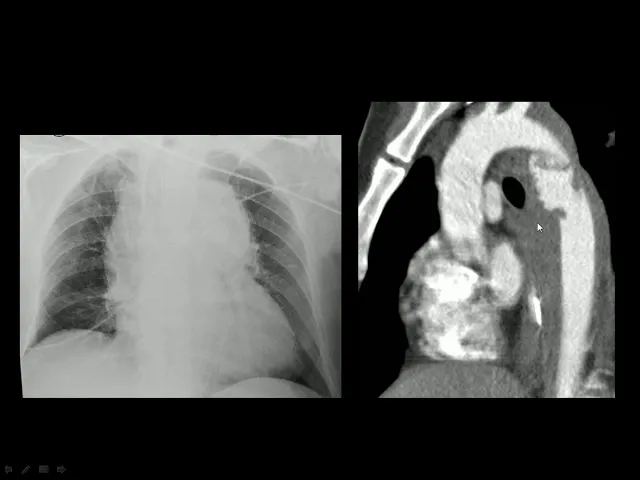

de hematomas deste final e possível lesão traumática da horta veja que esse outro caso um grande alargamento o mediastino desvio da traquéia para a direita e na tomografia computadorizada do tórax com contraste o ideal é que se faça um anjo tomografia a angiotomografia com cortes finos para fazer as reconstruções você observa que a horta vamos seguindo arco da horta exatamente na horta descendente no início da horta descendente na região do extremo você veja flaps da íntima phelps da parede da aorta ea formação de pseudo neurismene com múltiplas irregularidades então é uma lesão traumática da ordem

e observe que ao redor essa opacificação essa opacidade representa hematoma do mediastino aqui ao redor da wharton vejamos mais dois casos reconstruções sagitais da anjo tomografia de tórax você veja aqui a hora descendo ambiente o arco da horta e quando forma horta descendente você vê aqui uma formação um aneurisma ática sacular exatamente na topografia típica da lesão traumática da horta este caso é atípico porque a lesão com o pseudônimo está um pouco abaixo e nesse caso a via que também um derrame pleural esquerda um hemotórax nos courts axiais da tomografia o que nós vamos ver

você veja aqui a ordem ascendente normal na hora da descendente e veja aqui um flap da íntima uma linha uma imagem linear cruzando a luz e que então você vai ter uma luz verdadeira e uma falsa luz do pseudo neuri zuma traumático nós temos nesse outro caso a horta ascendente veia cava superior tronco da artéria pulmonar terra como na direita e esquerda ea horta descendente você veja ali o fé pi da íntima dividindo em duas luzes nello's verdadeira e o alos do pseudônimo orismar então também em caso de lesão traumática nesse caso existe também derrame